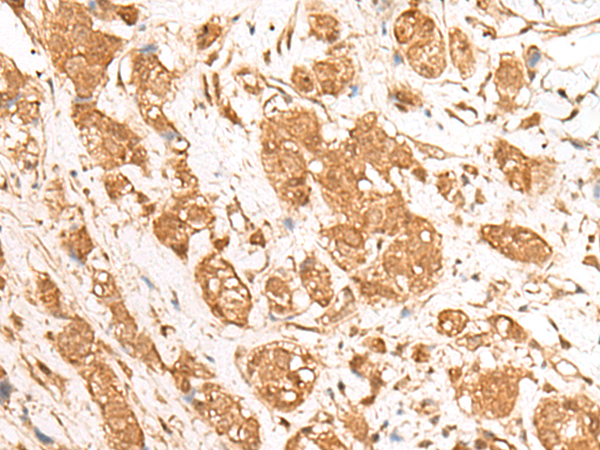

The image is immunohistochemistry of paraffin-embedded Human thyroid cancer tissue using P13444(GANC Antibody) at dilution 1/55. (Original magnification: ×200) |

The image is immunohistochemistry of paraffin-embedded Human breast cancer tissue using P13444(GANC Antibody) at dilution 1/55. (Original magnification: ×200) |